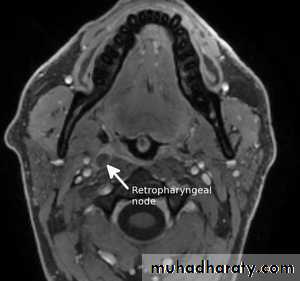

6. Retropharyngeal lymph nodes

A few nodes lie in the fascia on the posterior wall of the upper pharynx, in a plane just anterior to the mastoid process.They drain lymph from the oral and nasal parts of the pharynx, the palate, nose, and air sinuses, the auditory tube and middle ear.